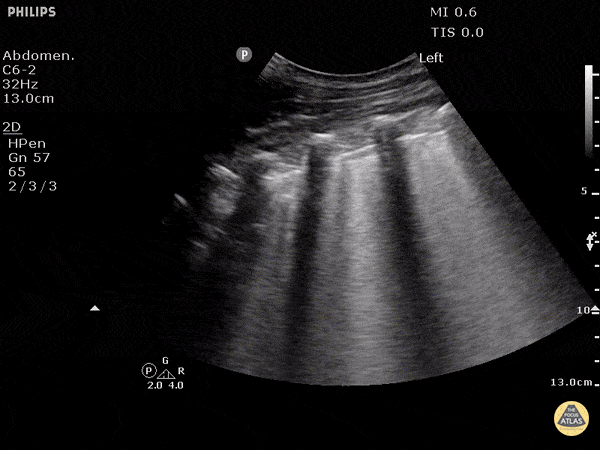

A 34-year-old man with alcohol use disorder presents with fever, profound hypotension, and severe respiratory distress. He is intubated in the ED and started on vasopressors and broad-spectrum antibiotics. Vitals: T 39.4°C, HR 138, BP 74/42, RR 34 before intubation, SpO₂ 82% on non-rebreather. Exam: toxic-appearing, cool extremities, markedly decreased air entry at the left base, coarse crackles over the left hemithorax. Blood cultures later grow MRSA, and CT chest shows left greater than right pleural effusions with left lung consolidation. A left lung ultrasound clip is shown. What are the ultrasound findings, and what is the most likely diagnosis?

What is complex loculated pleural effusion?

What is septic shock due to empyema?